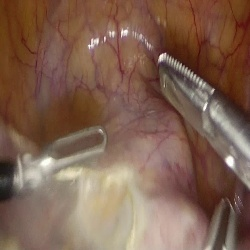

Large Vision-Language Models offer a new paradigm for AI-driven image understanding, enabling models to perform tasks without task-specific training. This flexibility holds particular promise across medicine, where expert-annotated data is scarce. Yet, VLMs' practical utility in intervention-focused domains--especially surgery, where decision-making is subjective and clinical scenarios are variable--remains uncertain. Here, we present a comprehensive analysis of 11 state-of-the-art VLMs across 17 key visual understanding tasks in surgical AI--from anatomy recognition to skill assessment--using 13 datasets spanning laparoscopic, robotic, and open procedures. In our experiments, VLMs demonstrate promising generalizability, at times outperforming supervised models when deployed outside their training setting. In-context learning, incorporating examples during testing, boosted performance up to three-fold, suggesting adaptability as a key strength. Still, tasks requiring spatial or temporal reasoning remained difficult. Beyond surgery, our findings offer insights into VLMs' potential for tackling complex and dynamic scenarios in clinical and broader real-world applications.